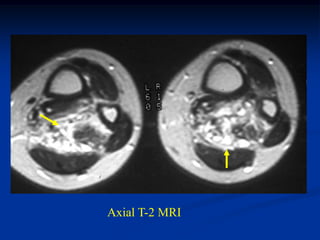

Case #1198.3 CT scan 4/06 71 year old male with painless soft mass in adductor compartment in 06 which became painful with recent growth in 09

Axial T-1 upper T-2 upper T-2 lower Cor STIR